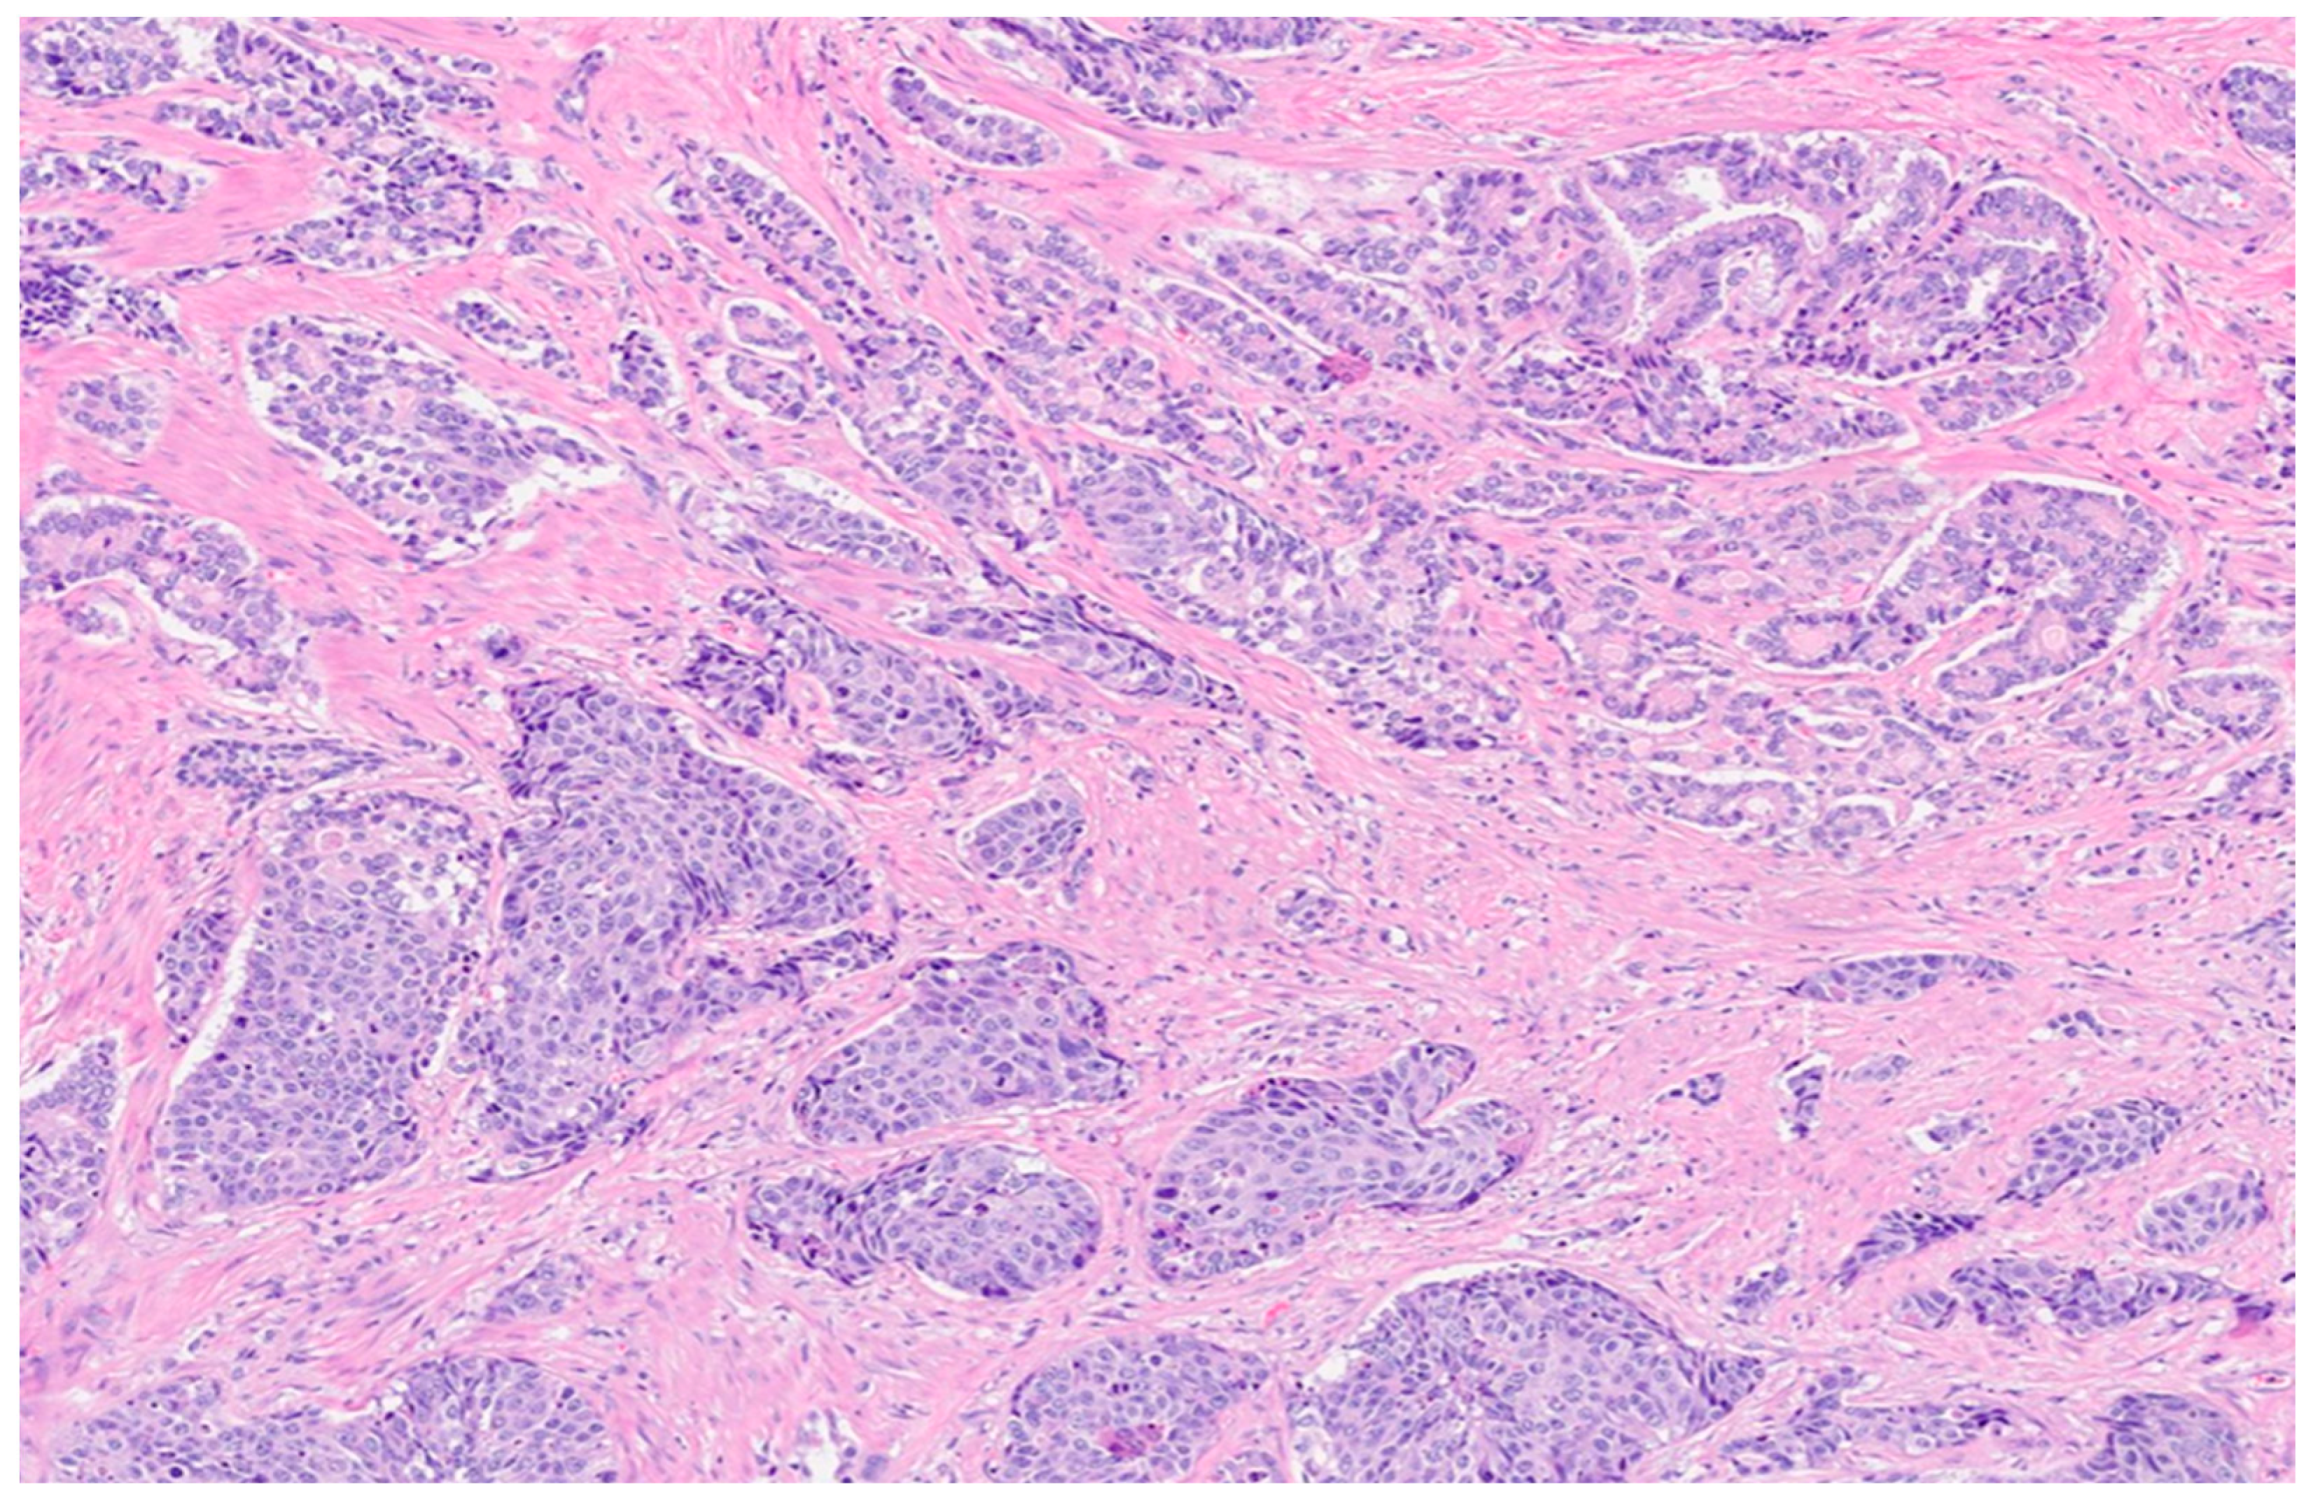

- Alhamar, M.; Vladislav, T.; Smith, S.C.; Gao, Y.; Cheng, L.; Favazza, L.A.; Alani, A.M.; Ittmann, M.M.; Riddle, N.D.; Whiteley, L.J.; et al. Gene fusion characterisation of rare aggressive prostate cancer variants—Adenosquamous carcinoma, pleomorphic giant-cell carcinoma, and sarcomatoid carcinoma: An analysis of 19 cases. Histopathology 2020, 77, 890–899. [Google Scholar] [CrossRef] [PubMed]